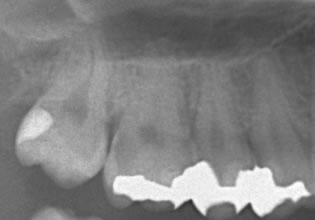

症例紹介

術 前 術 中 術 後

オーキッド|虫歯治療② オーキッド|虫歯治療⑤ オーキッド|虫歯治療③ オーキッド|虫歯治療④ オーキッド|虫歯治療⑥